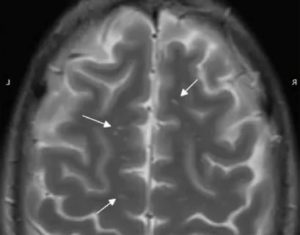

Справочно. Лучше всего визуализируются очаги глиоза на МРТ либо КТ-аппаратах.

Эти современные приборы позволяют с высокой точностью выявить сосудистые изменения, опухолевые процессы, патологические участки в белом веществе лобных долей, очаги кровоизлияний, ишемическое поражение.

Диагностика глиоза головного мозга основывается на данных КТ и МРТ:

- Магнитно-резонансная томография, является приоритетным методом для выявления таких отклонений. Помощью этого метода, специалист увидит очаги глиоза в мозге, выяснит степень распространенности и определит точную причину возникновения болезни.

- В случае глиоза, обычно в заключении МРТ может быть написано – «картина очага глиоза в левой (правой) лобной доли».

- Если очаги множественные, то данная методика выявит все места их локализации и масштабы гибели нейронов.

- Также магнитно-резонансный томограф определит причину возникновения таких очагов.

- Если виновником отмирания нервных клеток стало заболевание сосудистого характера, то в заключении МРТ будет написано – «картина единичного (множественных) очагов глиоза в белом веществе головного мозга – вероятно, сосудистого генеза». Подробнее о сосудистом генезе головного мозга и что это такое читайте в нашей аналогичной статье.